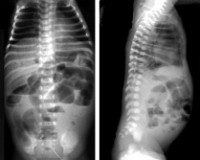

Ведущую роль в диагностике некротического энтероколита новорожденных играют инструментальные методы: рентгенография, УЗИ, КТ и МРТ. Они дают возможность визуализировать отек стенок кишечного тракта, плюс-ткань, наличие воздуха в брюшной полости, в просвете портальной или печеночной вен, а также отсутствие перистальтики на серии последовательных снимков. В педиатрии для подтверждения диагноза «некротический энтероколит новорожденных» и определения стадии заболевания применяется шкала Walsh и Kliegman. При использовании данной шкалы учитываются присутствующие у ребенка соматические симптомы, проявления со стороны желудочно-кишечного тракта и рентгенологические признаки. В зависимости от количества и выраженности проявлений выделяют подозреваемый НЭК (1а и 2а ), явный НЭК (2а и 2б ), прогрессирующий НЭК (3а и 3б ). Это имеет существенное значение при выборе тактики лечения.